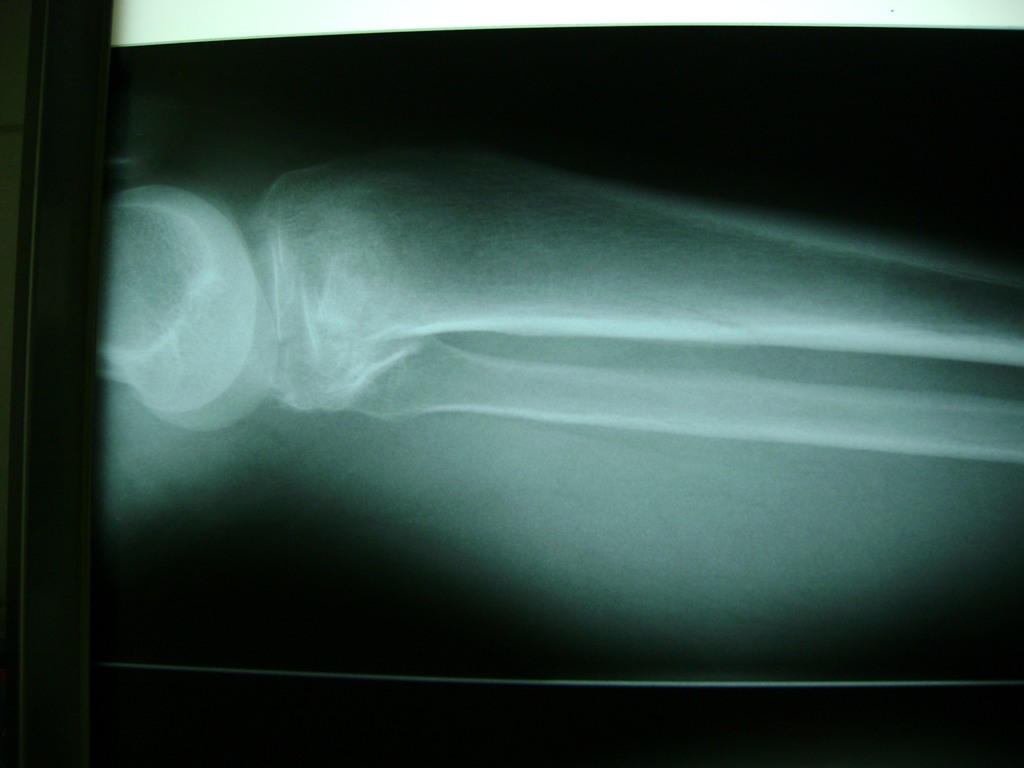

Cirugías de Rodillas